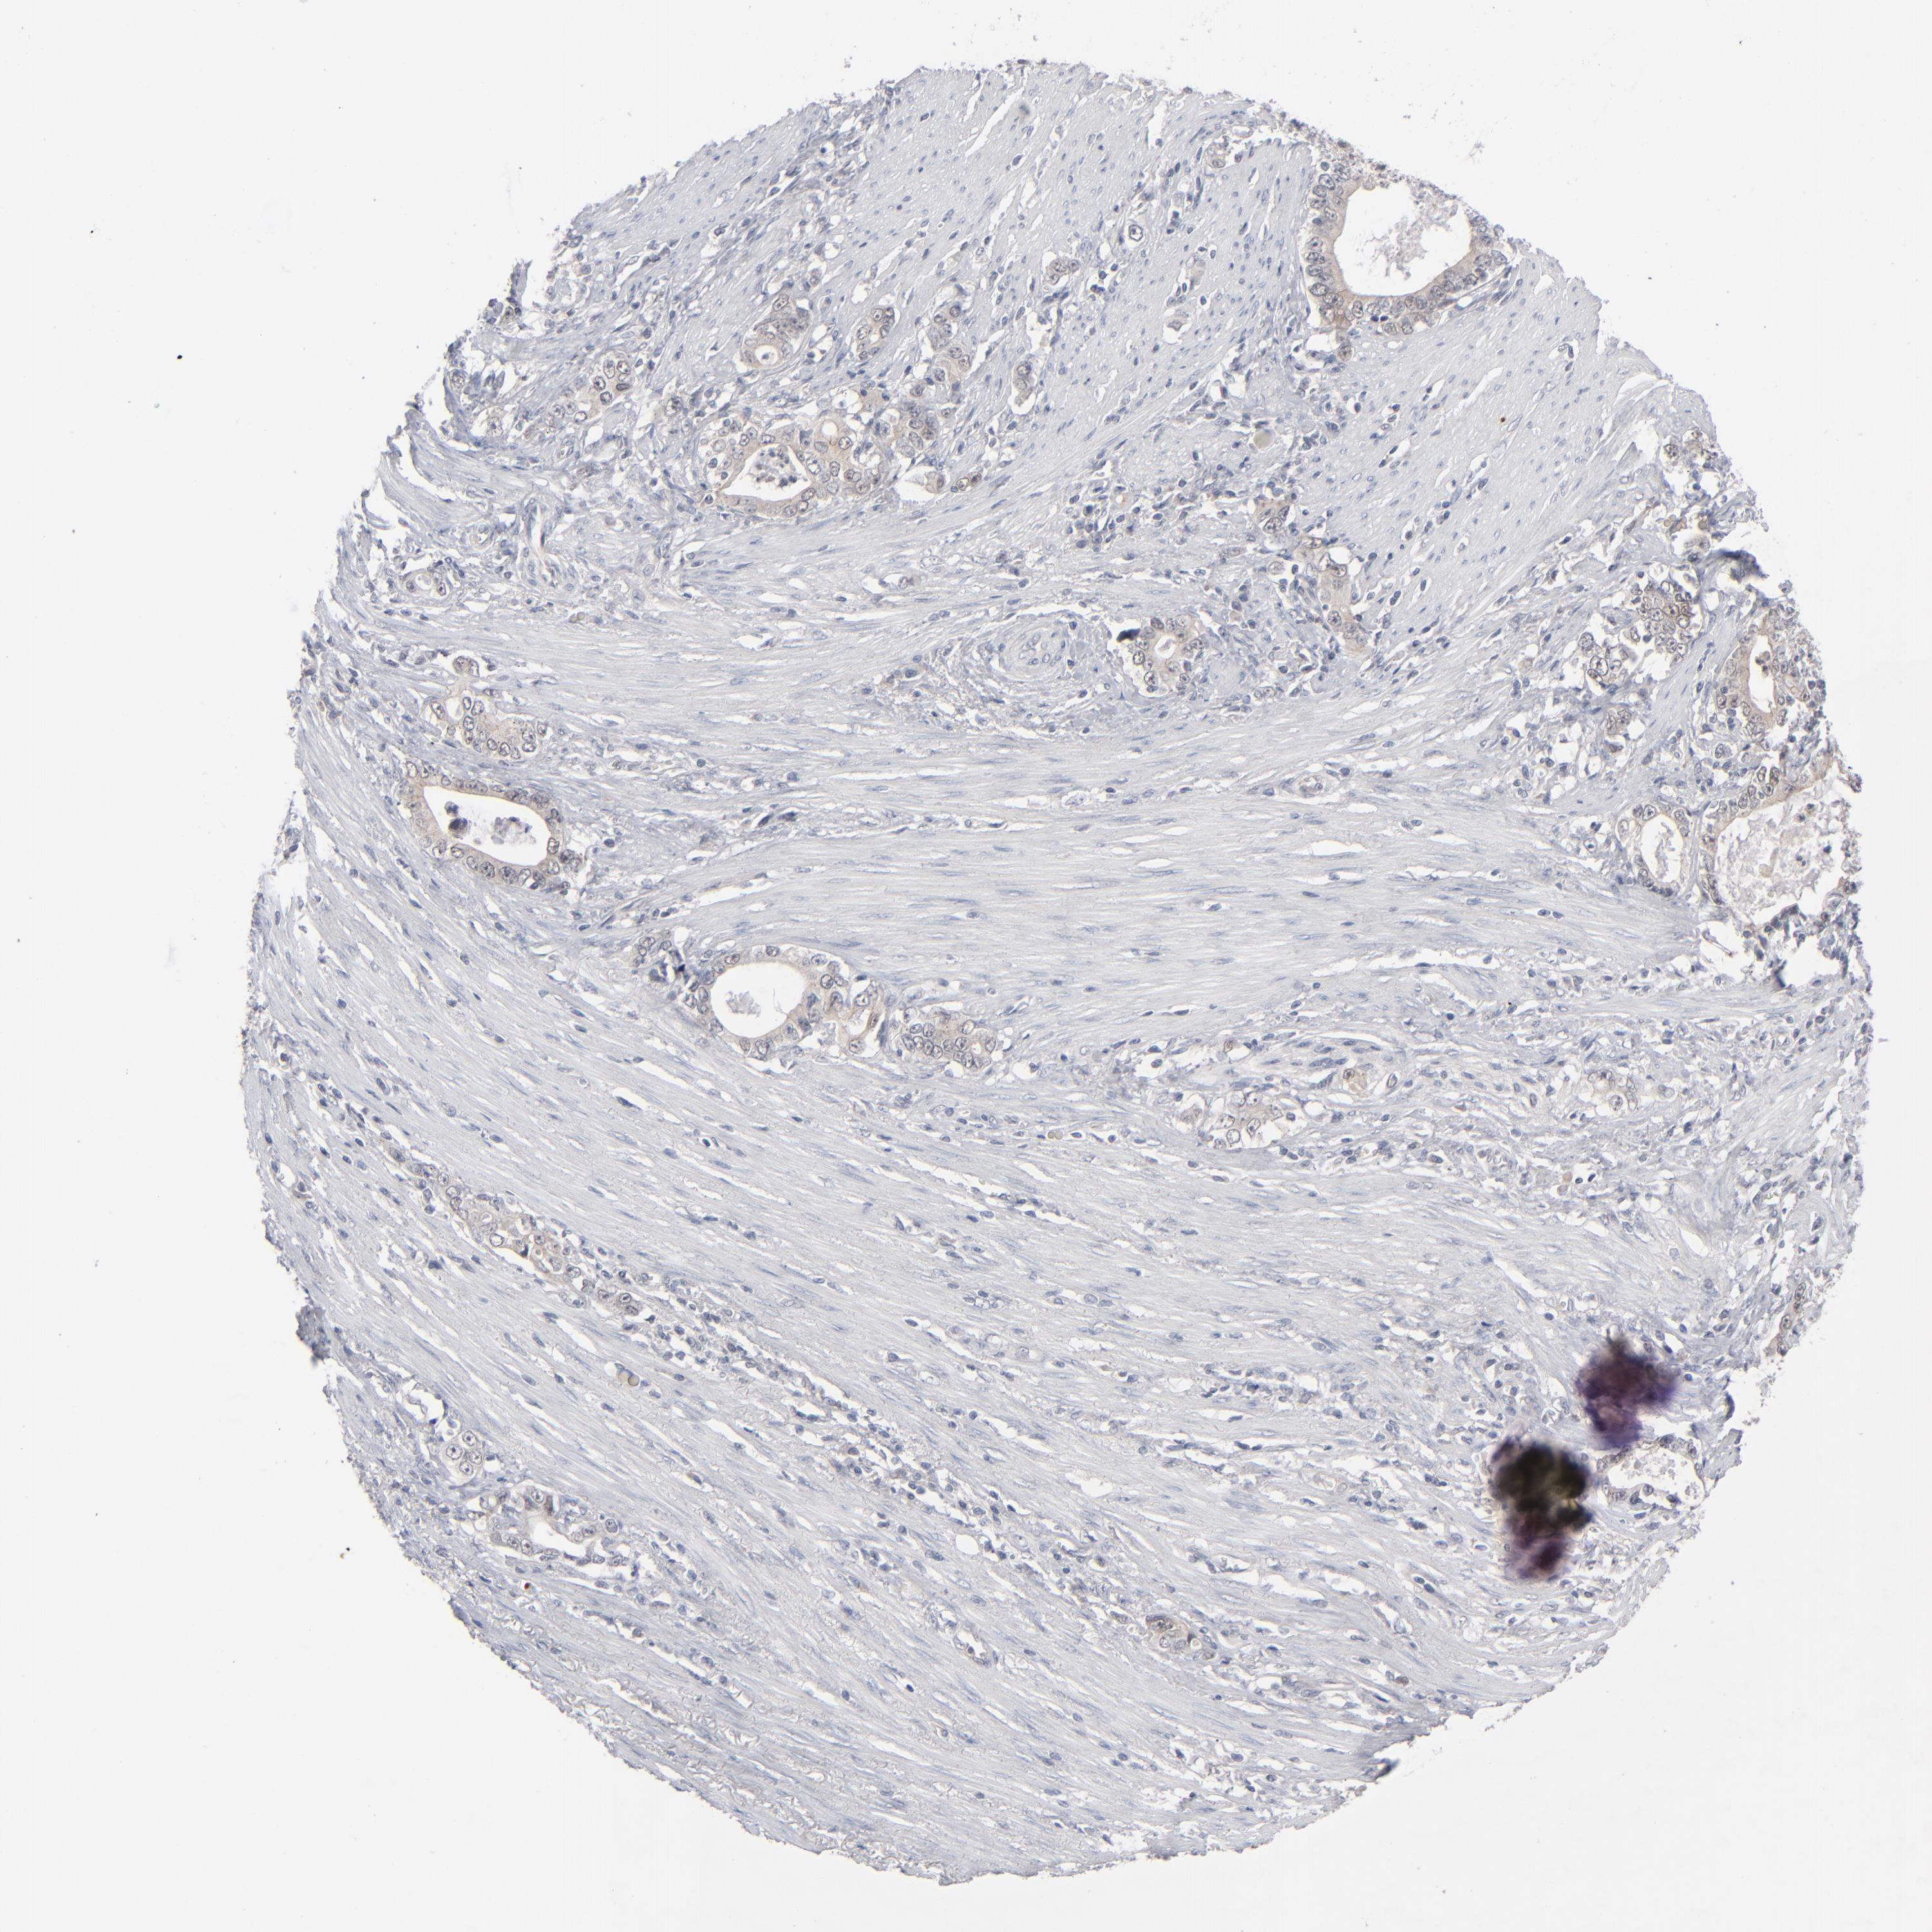

STOMACH CANCER - Protein expressioni

A mouse-over function shows sample information and annotation data. Click on an image to view it in a full screen mode. Samples can be filtered based on level of antibody staining by selecting one or several of the following categories: high, medium, low and not detected. The assay and annotation is described here.

Note that samples used for immunohistochemistry by the Human Protein Atlas do not correspond to samples in the TCGA dataset.

Antibody stainingi

Antibody staining in the annotated cell types in the current human tissue is reported as not detected, low, medium, or high, based on conventional immunohistochemistry profiling in selected tissues. This score is based on the combination of the staining intensity and fraction of stained cells.

Each image is clickable and will lead to virtual microscopy that enables deeper exploration of all samples and also displays staining intensity scores, fraction scores and subcellular localization as well as patient and tissue information for each sample.

Antibody HPA002033

Staining

High

Medium

Low

Not detected

Intensity

Strong

Moderate

Weak

Negative

Quantity

>75%

75%-25%

<25%

None

Location

Nuclear

Cytoplasmic/membranous

Cytoplasmic/membranous,nuclear

Adenocarcinoma, NOS

Adenocarcinoma, High grade